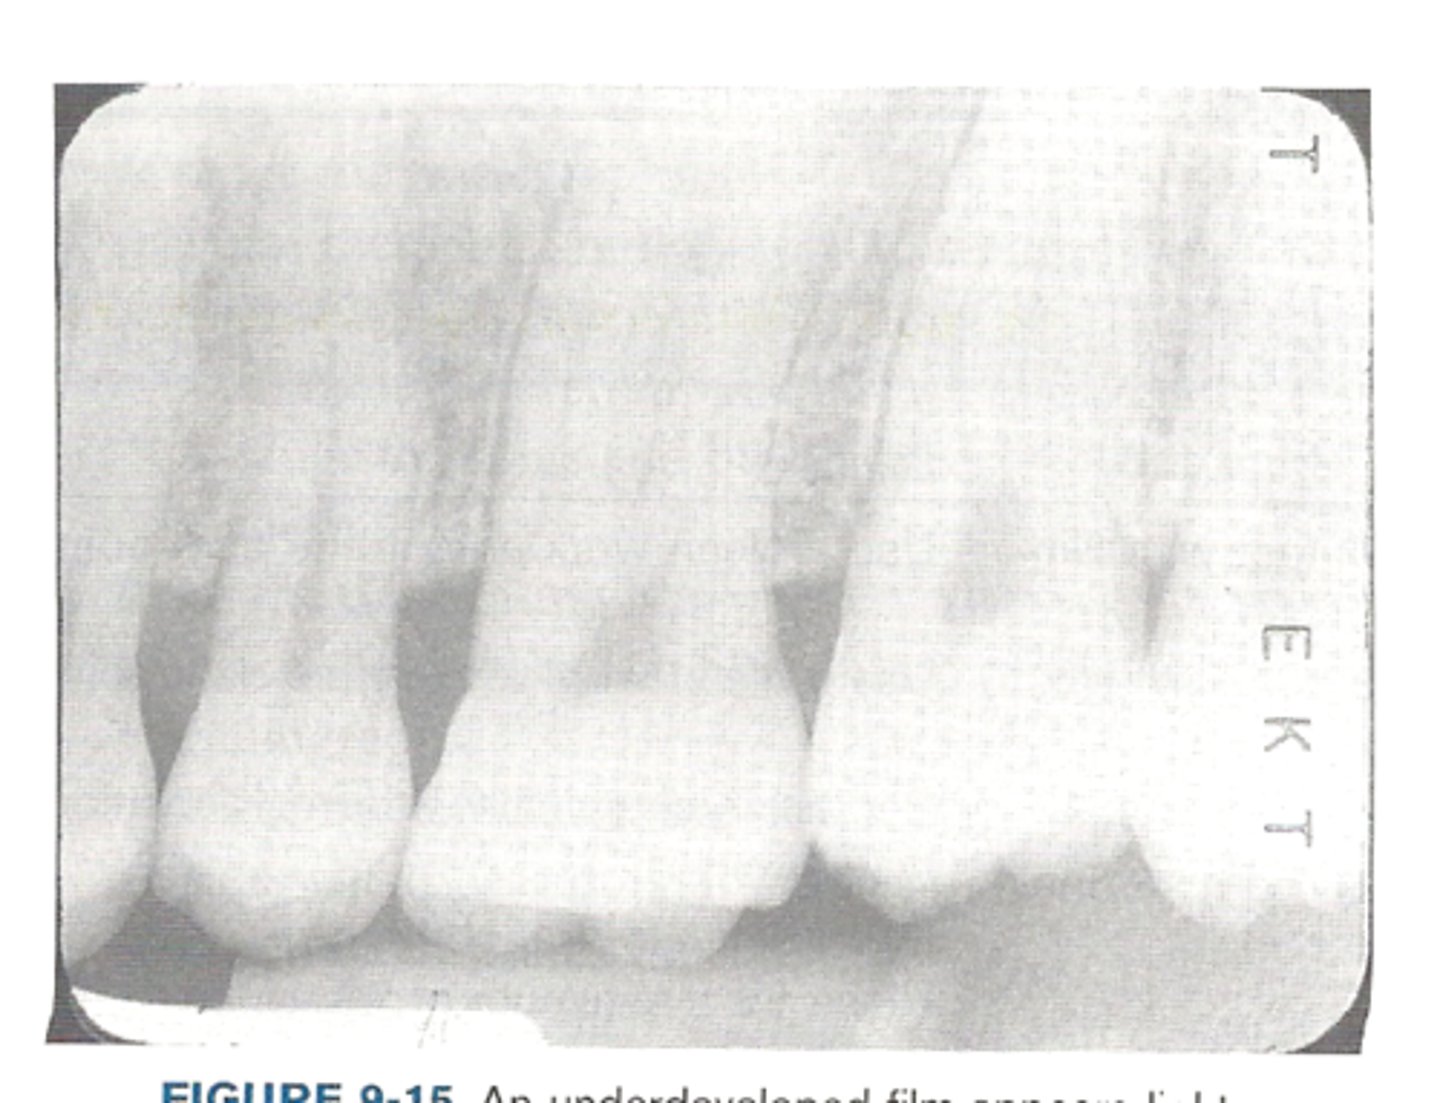

underdeveloped film

Light appearance due to:

•Inadequate development time

•Developer solution too cool

•Inaccurate timer or thermometer

•Depleted or contaminated developer solution

<p>Light appearance due to:</p><p>•Inadequate development time</p><p>•Developer solution too cool</p><p>•Inaccurate timer or thermometer</p><p>•Depleted or contaminated developer solution</p>